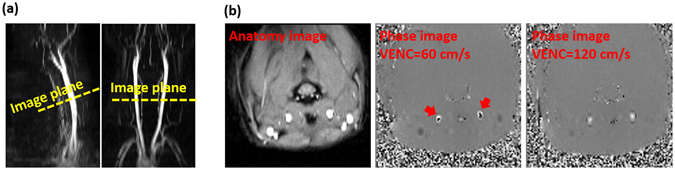

The purpose of this study was to evaluate the effects of cardiac-gated/non-gated sequences and VENC on blood flow, WSS, and artery area measurements. A total of 12 SD rats were scanned in this study. A 2D time-of-flight (TOF) angiogram was first made to obtain anatomical information on the localization of the CCA. The scanning parameters were TR/TE = 22/4.87 ms, flip angle = 90°, field of view (FOV) = 40 × 40 mm, matrix size = 256 × 256, slice thickness was 0.6 mm, and the NEX = 1. Following localization with the TOF angiogram, the image plane of the PC-MRI was targeted at the middle of CCA and perpendicular to the direction of blood flow (Fig. 5a). Next, both gated and non-gated PC-MRI scans were performed to determine the optimal settings for measuring the relevant hemodynamic parameters. For both gated and non-gated techniques, VENC values in the range of 60–120 cm/s with an interval of 10 cm/s were scanned twice in randomized order to estimate the CoV. The reproducibility experiment for each VENC setting was separated by other VENC settings to avoid measurement bias. Any velocity aliasing (usually at the center of CCAs) due to underestimated VENC parameters was corrected by post-processing24. With a VENC of 120 cm/s, no phase aliasing was observed in any rats (Fig. 5b). Other imaging parameters of the 2D time-resolved PC-MRI scans were as follows: TR/TE = 15.55/4.51 ms (minimum TR and TE), flip angle = 30°, FOV = 40 × 40 mm2, matrix size = 128 × 128, slice thickness was 2 mm, and the NEX = 8. Unidirectional VENC was done in the through-plane direction. The temporal resolution was around 31 ms. For the cardiac-gated technique, a prospective ECG gating technique was used to synchronize the heartbeat and acquire flow information within 90% of the R–R intervals. Total scan durations were 3.5 mins and 16 s for gated and non-gated sequences, respectively.

Figure 5.

Illustration of the position of PC-MRI scans and representative images. (a) Example of PC-MRI slice position on the reconstructed sagittal and coronal view from the time-of-flight (TOF) angiogram. The yellow line indicates the image plane of PC-MRI at the level of middle of common carotid artery (CCA). (b) Anatomy and phase images from a representative rat. Red arrows indicate the phase aliasing when VENC of 60 cm/s was used. With higher VENC setting, the phase aliasing vanished.